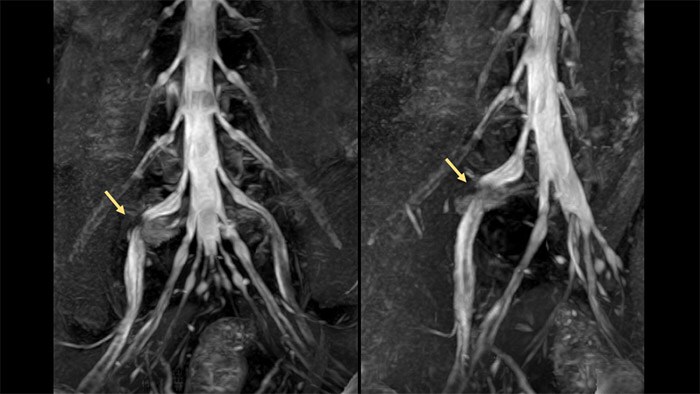

Example of standardized tissue sodium content map (left) and example of MR lymphangiography and maximum intensity projection (MIP) reconstruction (right).

“We're interested in applying sodium imaging in long term clinical trials of lipedema and lymphedema to understand the development of advanced disease severity, and if sodium, early in the disease process, could be a marker of risk for lymphatic dysfunction,” she says. “Also fascinating are the features of lymphedema with lymph stasis in the body, that we observed with some vascular imaging techniques that we've worked on over the years with our collaborators in radiology and vascular medicine.”